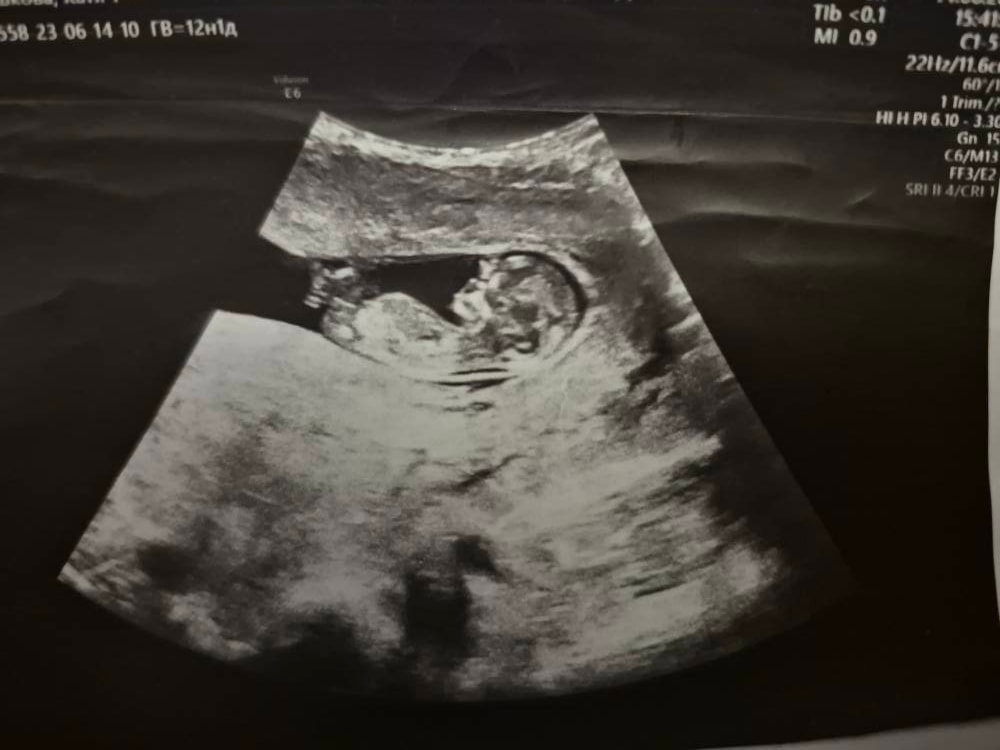

в12.1 сказали, что девочка

Изображение

только такое фото осталось

В 12 недель писюна ещё нет, рано ещё, только половой бугорок, в он и у девочек есть на таком сроке) мне пол не говорили (у нас принципиально на первом скрининге не говорят), но сама увидела, что девочка - половой бугорок четко параллельно позвоночнику был, у мальчиков он под углом располагается.

Ксеня, да. Собственно, на этом сроке пол так и предполагают (определяют - громко сказано, вероятность ошибки большая пока): у девочек половой бугорок "лежит" или совсем немного приподнят, у мальчиков под бОльшим углом торчит.